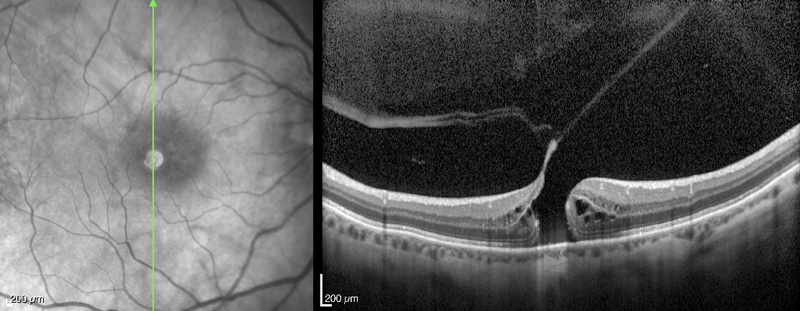

Maculopatía traccional miópica

Actualmente, con la OCT es posible evaluar las alteraciones de la interfase vitreomacular en ojos con alta miopía. Uno de estos fenómenos es la rotura o esquisis que se produce con frecuencia en ojos con alta miopía y estafiloma posterior. La esquisis es casi imposible de ver en la exploración biomicroscópica. Según los estudios realizados por Benhamou

et al41 en pacientes con alta miopía, con una media de refracción de -15,2 D, existirían dos patrones de esquisis. En el patrón de esquisis externa, la retina se separa en una capa interna gruesa y una capa externa más fina por un espacio ancho hiporreflectivo. En algunos casos pueden apreciarse en la OCT unos puentes lineales que atraviesan este espacio hiporreflectivo. El otro patrón sería de esquisis interna, en la cual la separación de la retina divide una capa interna fina de una capa externa gruesa. El patrón más frecuente es el de esquisis externa, pero con componentes que pueden variar desde esquisis internas y desprendimientos maculares hasta AL o AMEC. También puede detectarse, en algunos casos, adherencia de la hialoides posterior traccionando. La presencia de un estafiloma posterior también es frecuente

39-42.

En conjunto, puede afirmarse que las esquisis son procesos bastante estables, con una progresión lenta. La presencia de una tracción vitreomacular en estos pacientes puede llevar a la formación de AMEC. Un porcentaje pequeño de ellos lo pueden desarrollar de forma asintomática. Esto se correlaciona con la presencia de tejido epiretiniano, el grado de miopía y la juventud del paciente

43,44.

Aunque la naturaleza de la tracción y la importancia de su patogenia en esta enfermedad no se entiende de manera clara, numerosas publicaciones han documentado la mejoría o la resolución de la esquisis miópica tras la vitrectomía con eliminación del vítreo cortical posterior y/o pelado de la membrana limitante interna. También se cree que fuerzas de tracción de la retina hacia el centro de la fóvea a lo largo de las arteriolas pueden estar relacionadas con la patogénesis de las afecciones vitreoretinianas miópicas, incluyendo la retinosquisis y la formación del agujero macular

45,46 (

Figura 30. Agujero macular miópico, con tracción y esquisis macular.

Figura 31. Agujero macular miópico, con tracción y esquisis macular, al mes de realizar cirugía de vitrectomía.

Figura 32. Agujero macular miópico, con tracción y esquisis macular, a los 6 meses de realizar cirugía de vitrectomía.

Figura 33. Esquisis con tracción en paciente miope con estafiloma posterior.